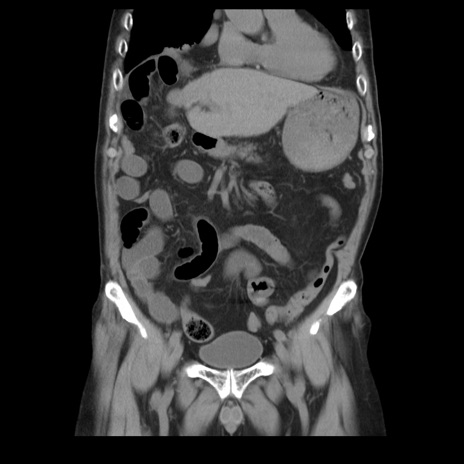

症例21(冠状断像)

【症例】70歳代男性

【主訴】腹痛

【現病歴】肝硬変・肝細胞癌にてかかりつけの方。約9時間前に食後より腹痛出現。症状が徐々に増悪し、嘔吐出現したため来院。

【既往歴】肝硬変、肝細胞癌(RFA、TACE後)

【身体所見】意識清明、表情苦悶様、BT 36℃、BP 129/78mmHg、P 88bpm、SpO2 97%(RA)、右上腹部から心窩部にかけて圧痛あり、反跳痛なし、筋性防御あり。

【データ】WBC 5800、CRP 0.16